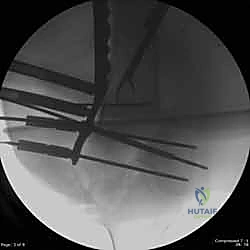

قبل بدء الجراحة، يتم رسم خطة دقيقة. يتم وضع المريض على طاولة العمليات المجهزة بأشعة (C-Arm) لضمان التصوير الفوري أثناء الجراحة.

يستخدم الدكتور هطيف تقنيات الفتح الجراحي المحدود (Minimally Invasive Plate Osteosynthesis - MIPO) كلما أمكن ذلك، للحفاظ على التروية الدموية للعظم وتسريع الالتئام. يتم عمل شق جانبي بعناية للوصول إلى منطقة الكسر دون الإضرار بالعضلات المحيطة.

المرحلة الثالثة: إرجاع العظم (Reduction)

هذه هي الخطوة الأكثر أهمية. يقوم الدكتور هطيف بإعادة القطع العظمية المكسورة إلى مكانها التشريحي الأصلي. إذا كان الكسر ممتداً داخل المفصل، يتم تثبيت السطح المفصلي أولاً باستخدام مسامير دقيقة لضمان سطح أملس يمنع الاحتكاك والخشونة مستقبلاً.